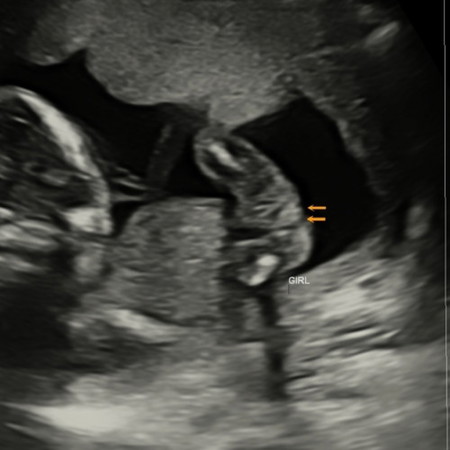

SCAN GENDER 17W

scan 17w dah nampak 3line. tapi mommy risau kena scam takut2 rupanya telor. boleh jadi tak? haha baju pink2 dah beli 🤣🤣 eksited punya pasal

InsyaAllah girl ni. Obvious 3 lines dier.

Girl ni